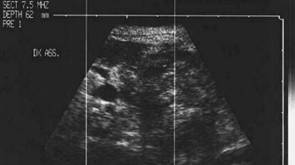

Lob drept, proiectie trasversala si longitudinala

Barbat de 65 ani. Recidiva voluminoasa

laterocervical dreapta dupa un neoplasm anaplazic cu celule fuzate; tratament -

chimioterapie si radioterapia. Carotida dreapta inglobata si infiltrata